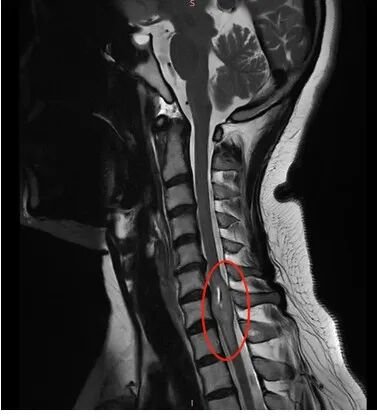

位于高位颈髓区域的海绵状血管瘤,由于病灶处于人体神经中枢的关键部位,始终被视为高风险疾病——可能引发瘫痪或呼吸骤停等严重并发症。患者面临的治疗决策往往处于两难境地:...

更新时间:2025-12-05 10:30:44

一位颅底术后患者复查时提出疑问:“医生,我脖子后面固定的钉子怎么弯了?会不会存在什么问题?”主刀医生对此进行了明确解释:该设计为特意进行的弯折处理,其目的不仅在于更好地适应...

更新时间:2025-11-28 10:28:32